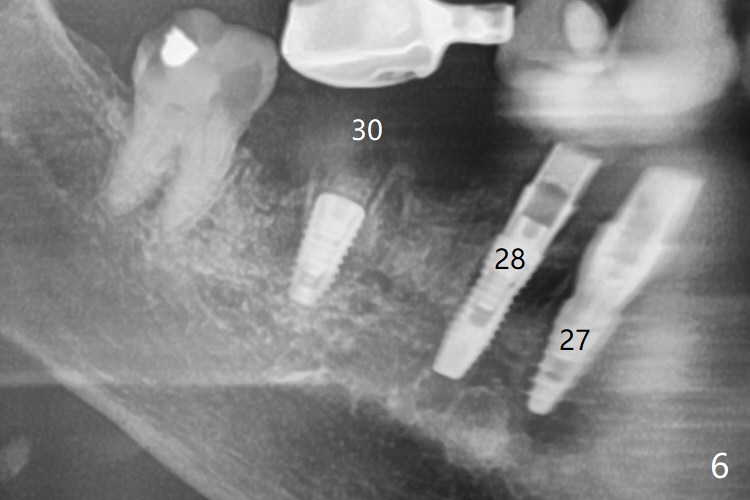

85岁女回诊所做27,28,30植牙,由于导板设计,所有7个残根需要拔除(图一,三),做过根管治疗牙齿(图一:箭头),如19,21号牙,颊侧骨板吸收比没做过的轻(图二,四:箭头(根尖穿孔))。30号牙根尖吸收多,使用短小植体(图五),根尖骨质少,初步稳定性差,不能即刻修复(图六),是这次手术最大欠缺的部分。原来准备在30号牙位做临时牙冠,局部托牙卡环恢复作用,还好27,28植体(图八)稳定性好,连体临时牙冠帮助托牙固定。27,28植体不足之处是放置太深,基台与牙槽骨(图八:*)接触,可能造成骨质吸收。其实27号植体(3.5x9mm)植入后必须去除,与基台连接后,一起徒手植入,所以深度控制不好。术后一个月10天病人回来做20和22号牙种植(拔牙后一,两个月),由于角化龈窄,切开导板植入,好处容易判断22号牙植体深度,植深后,两个植体周围放置骨粉(图九,十),然后胎盘膜(两个8x8毫米),4-0 PGA缝线。